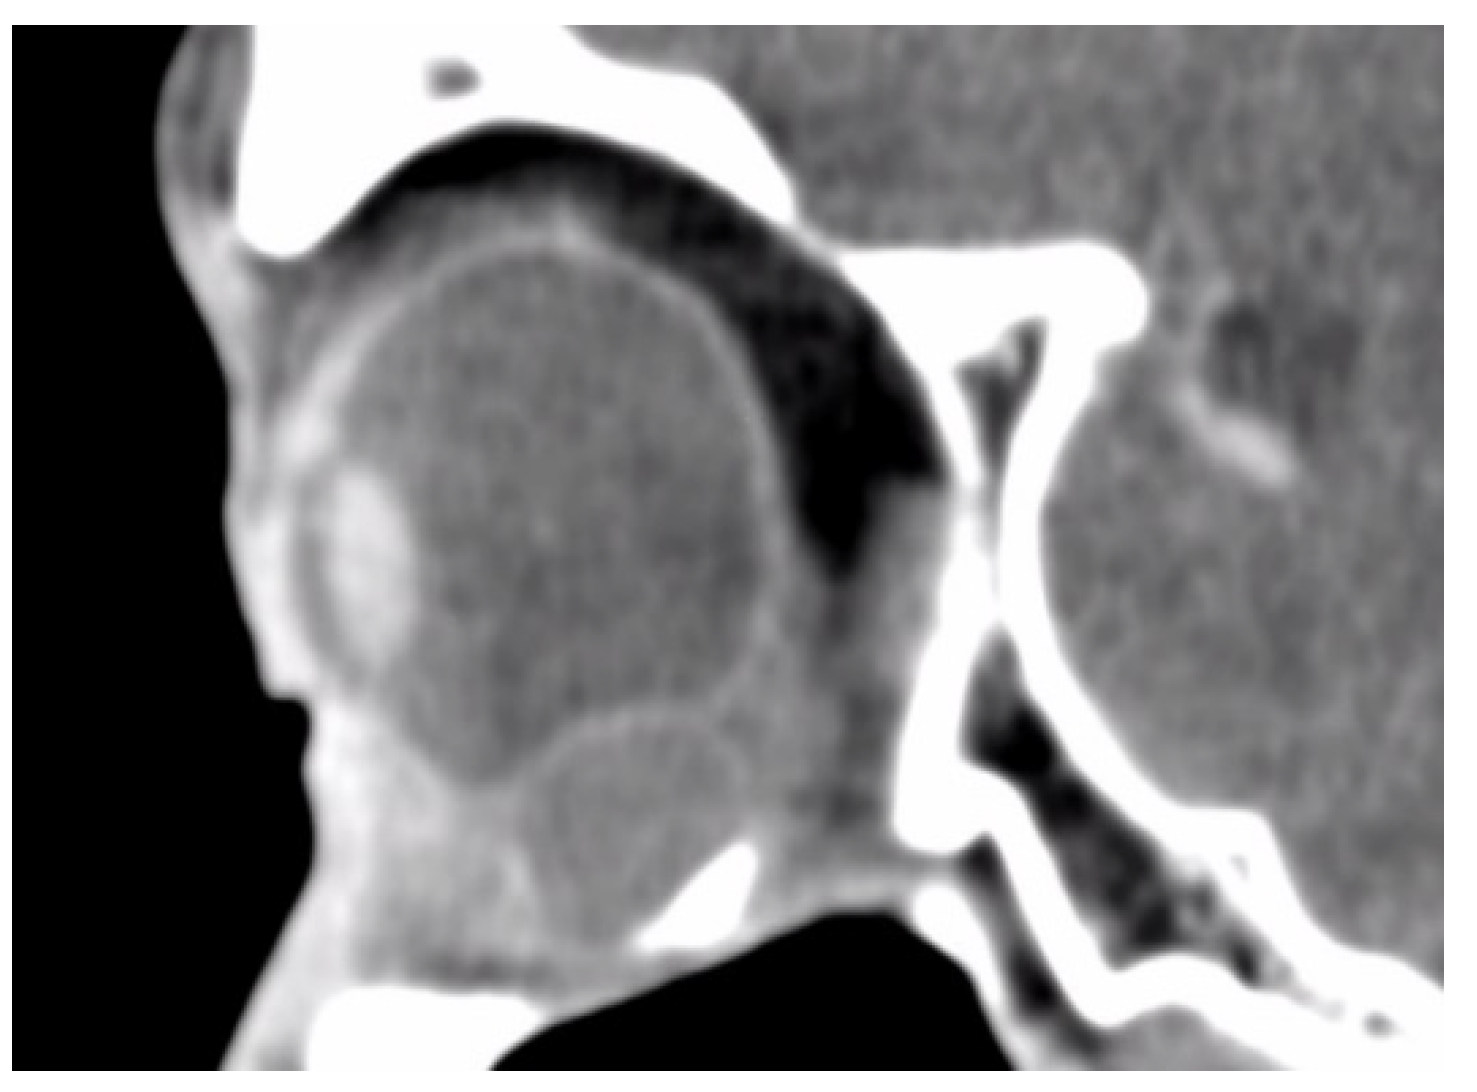

In total, we collected eleven cases; Table 1 summarizes the clinical data. One patient had bulbar atrophy before the diagnosis of swollen HSB (Figure 1). Table 2 shows the presenting symptoms of the patients. The symptoms included limitation of extraocular movement (ten eyes, 90.9%), ocular redness (eight eyes, 72.7%), ocular fullness (eight eyes, 72.7%), pain (six eyes, 54.5%), and exposed ocular foreign body (five eyes, 45.5%). Six patients (54.5%) received a correct diagnosis when referred to the medical center. Initial diagnoses other than swollen HSB included eyeball rupture (one eye, 9.1%), and orbital tumor (four eyes, 36.4%). Six patients (54.5%) had glaucoma in the diseased eyes and were treated with at least one combined form or two antiglaucoma medications before orbital HSB swelling was found. Four patients (66.7%) were male, but there was no significance of sex and glaucoma correlation according to Chi-Square analysis (p = 0.652). In the six patients with glaucoma, four cases had inadequate IOP control and one case received minimally invasive glaucoma surgery due to uncontrolled IOP one year before HSB removal. New onset of limitations of extraocular movement prompted the doctors to survey for orbital lesions. The typical CT image finding of HSB is a circumferential and homogenous mass around the globe. As this material usually swells when it absorbs water and forms a pseudocapsule around itself, CT images show an isointense signal with a vitreous and non-infiltrative lesion that deforms the eyeball. A scattered, and hyperintense signal, which corresponds to calcific change, can also be found around the swollen HSB (Figure 2). In MRI study, the HSB usually show hypointensity in T1-weighted images and hyperintensity in T2-weighted images, as these materials absorb water (Figure 3). According to the location of HSB in orbital CT, we categorized the HSB coverage into two groups: anterior-located (Figure 4) and posterior-located HSB (Figure 5). In the six patients with glaucoma, four (66.7%) showed posterior-located HSB. However, Fisher’s exact test of the relationship between the posterior-located HSB and glaucoma diagnosis did not reach clinical significance (p = 0.061).

Figure 2. Orbital CT showed a homogenous and hypointense mass with scattered hyperintense spots. This finding was compatible with hydrated hydrogel scleral buckles and dystrophyic calcification.